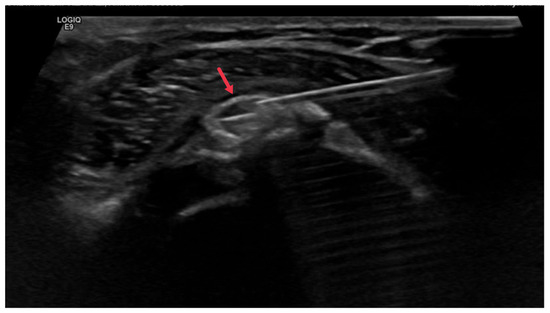

Gradient recalled echo (GRE) sequences can reveal hydroxyapatite deposits as areas of signal voids or hypointensity due to the magnetic susceptibility effects of the calcified material. This is particularly useful in early-stage HADD, where the amount of hydroxyapatite deposition may be minimal and harder to detect with other imaging techniques (Figure 6).

Figure 6. (A) Axial PD fat-saturated MRI image and (B) axial GRE sequence MRI of the right shoulder demonstrating a small well-defined low signal intensity calcification at the insertion of the supraspinatus tendon (red arrow). Note how the calcification is more visible and conspicuous on the GRE sequence (black arrow) due to a blooming artifact from the calcification.